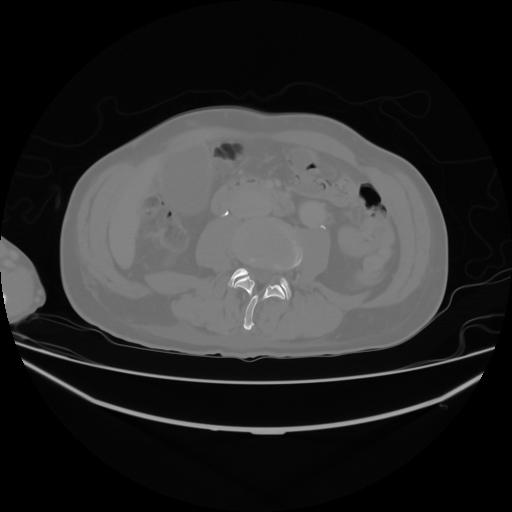

4 CUERPO,CE,Axial,3.0,CUERPO,,